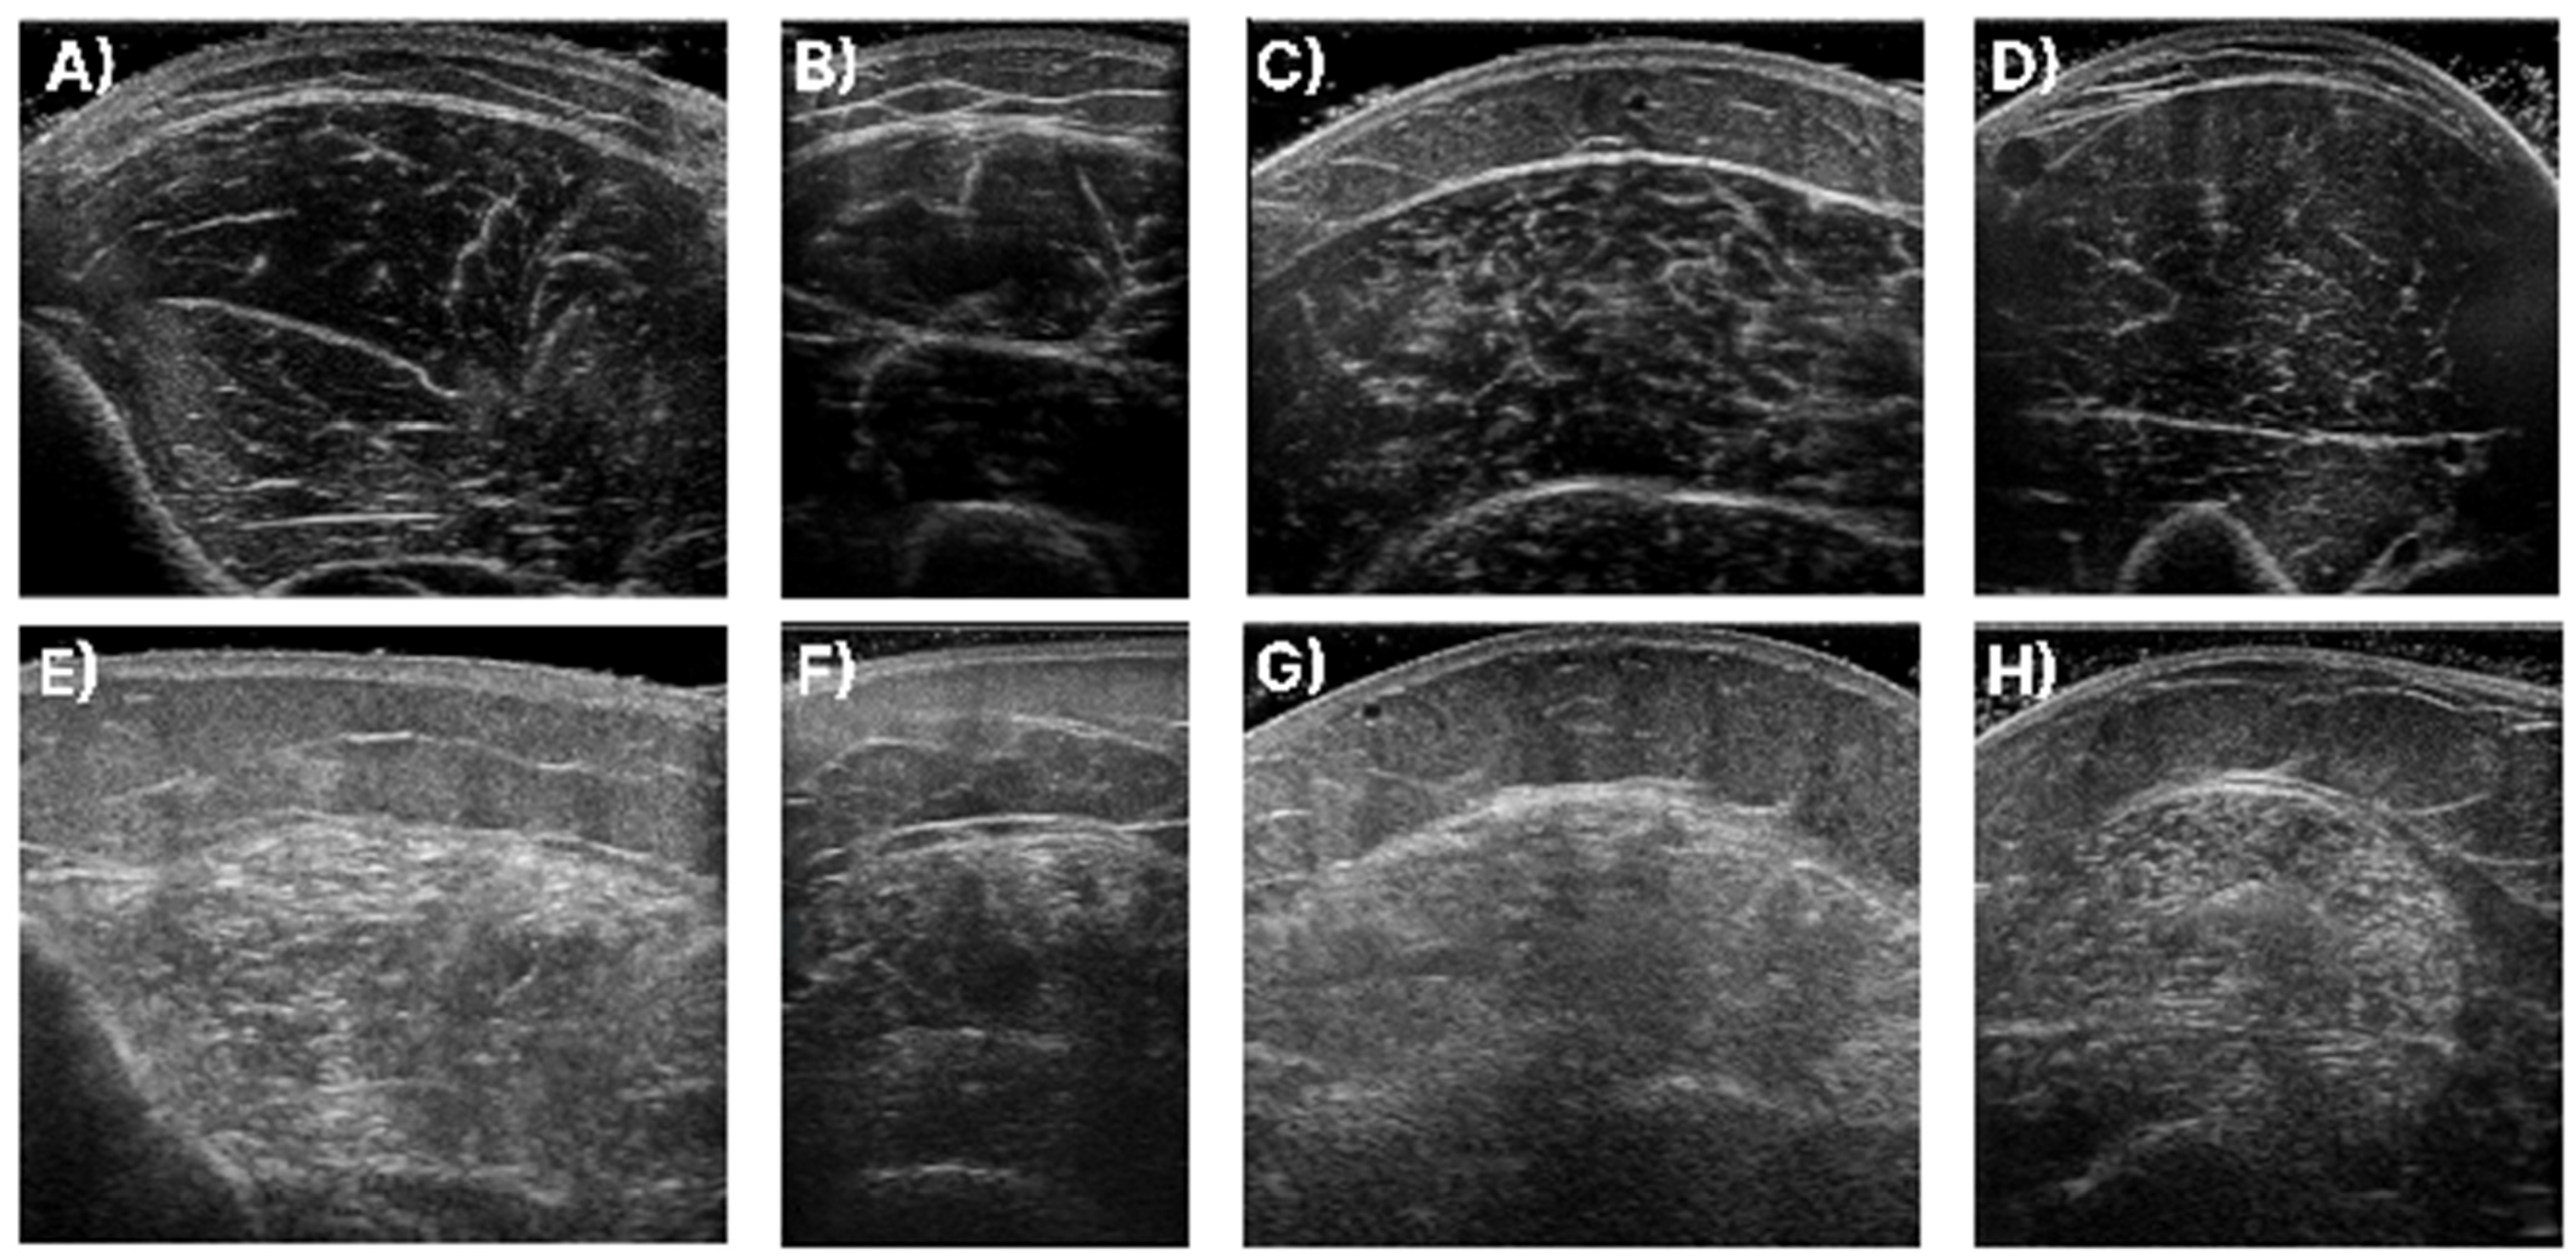

In Figure 1, samples of the studied muscles are presented for normal and high echogenicity images. It is observable in these images that the muscle aponeuroses, especially in the high echogenicity images, are hard to distinguish from the other muscle tissue, making the accurate localisation of the CSA more challenging.

Figure 1.

Sample of ultrasound recordings with normal and high echogenicity. (A,E) shows images from the T.A., (B,F) shows images from the R.F., (C,G) shows images extracted from the GCM, and finally, (D,H) are images of the B.B.